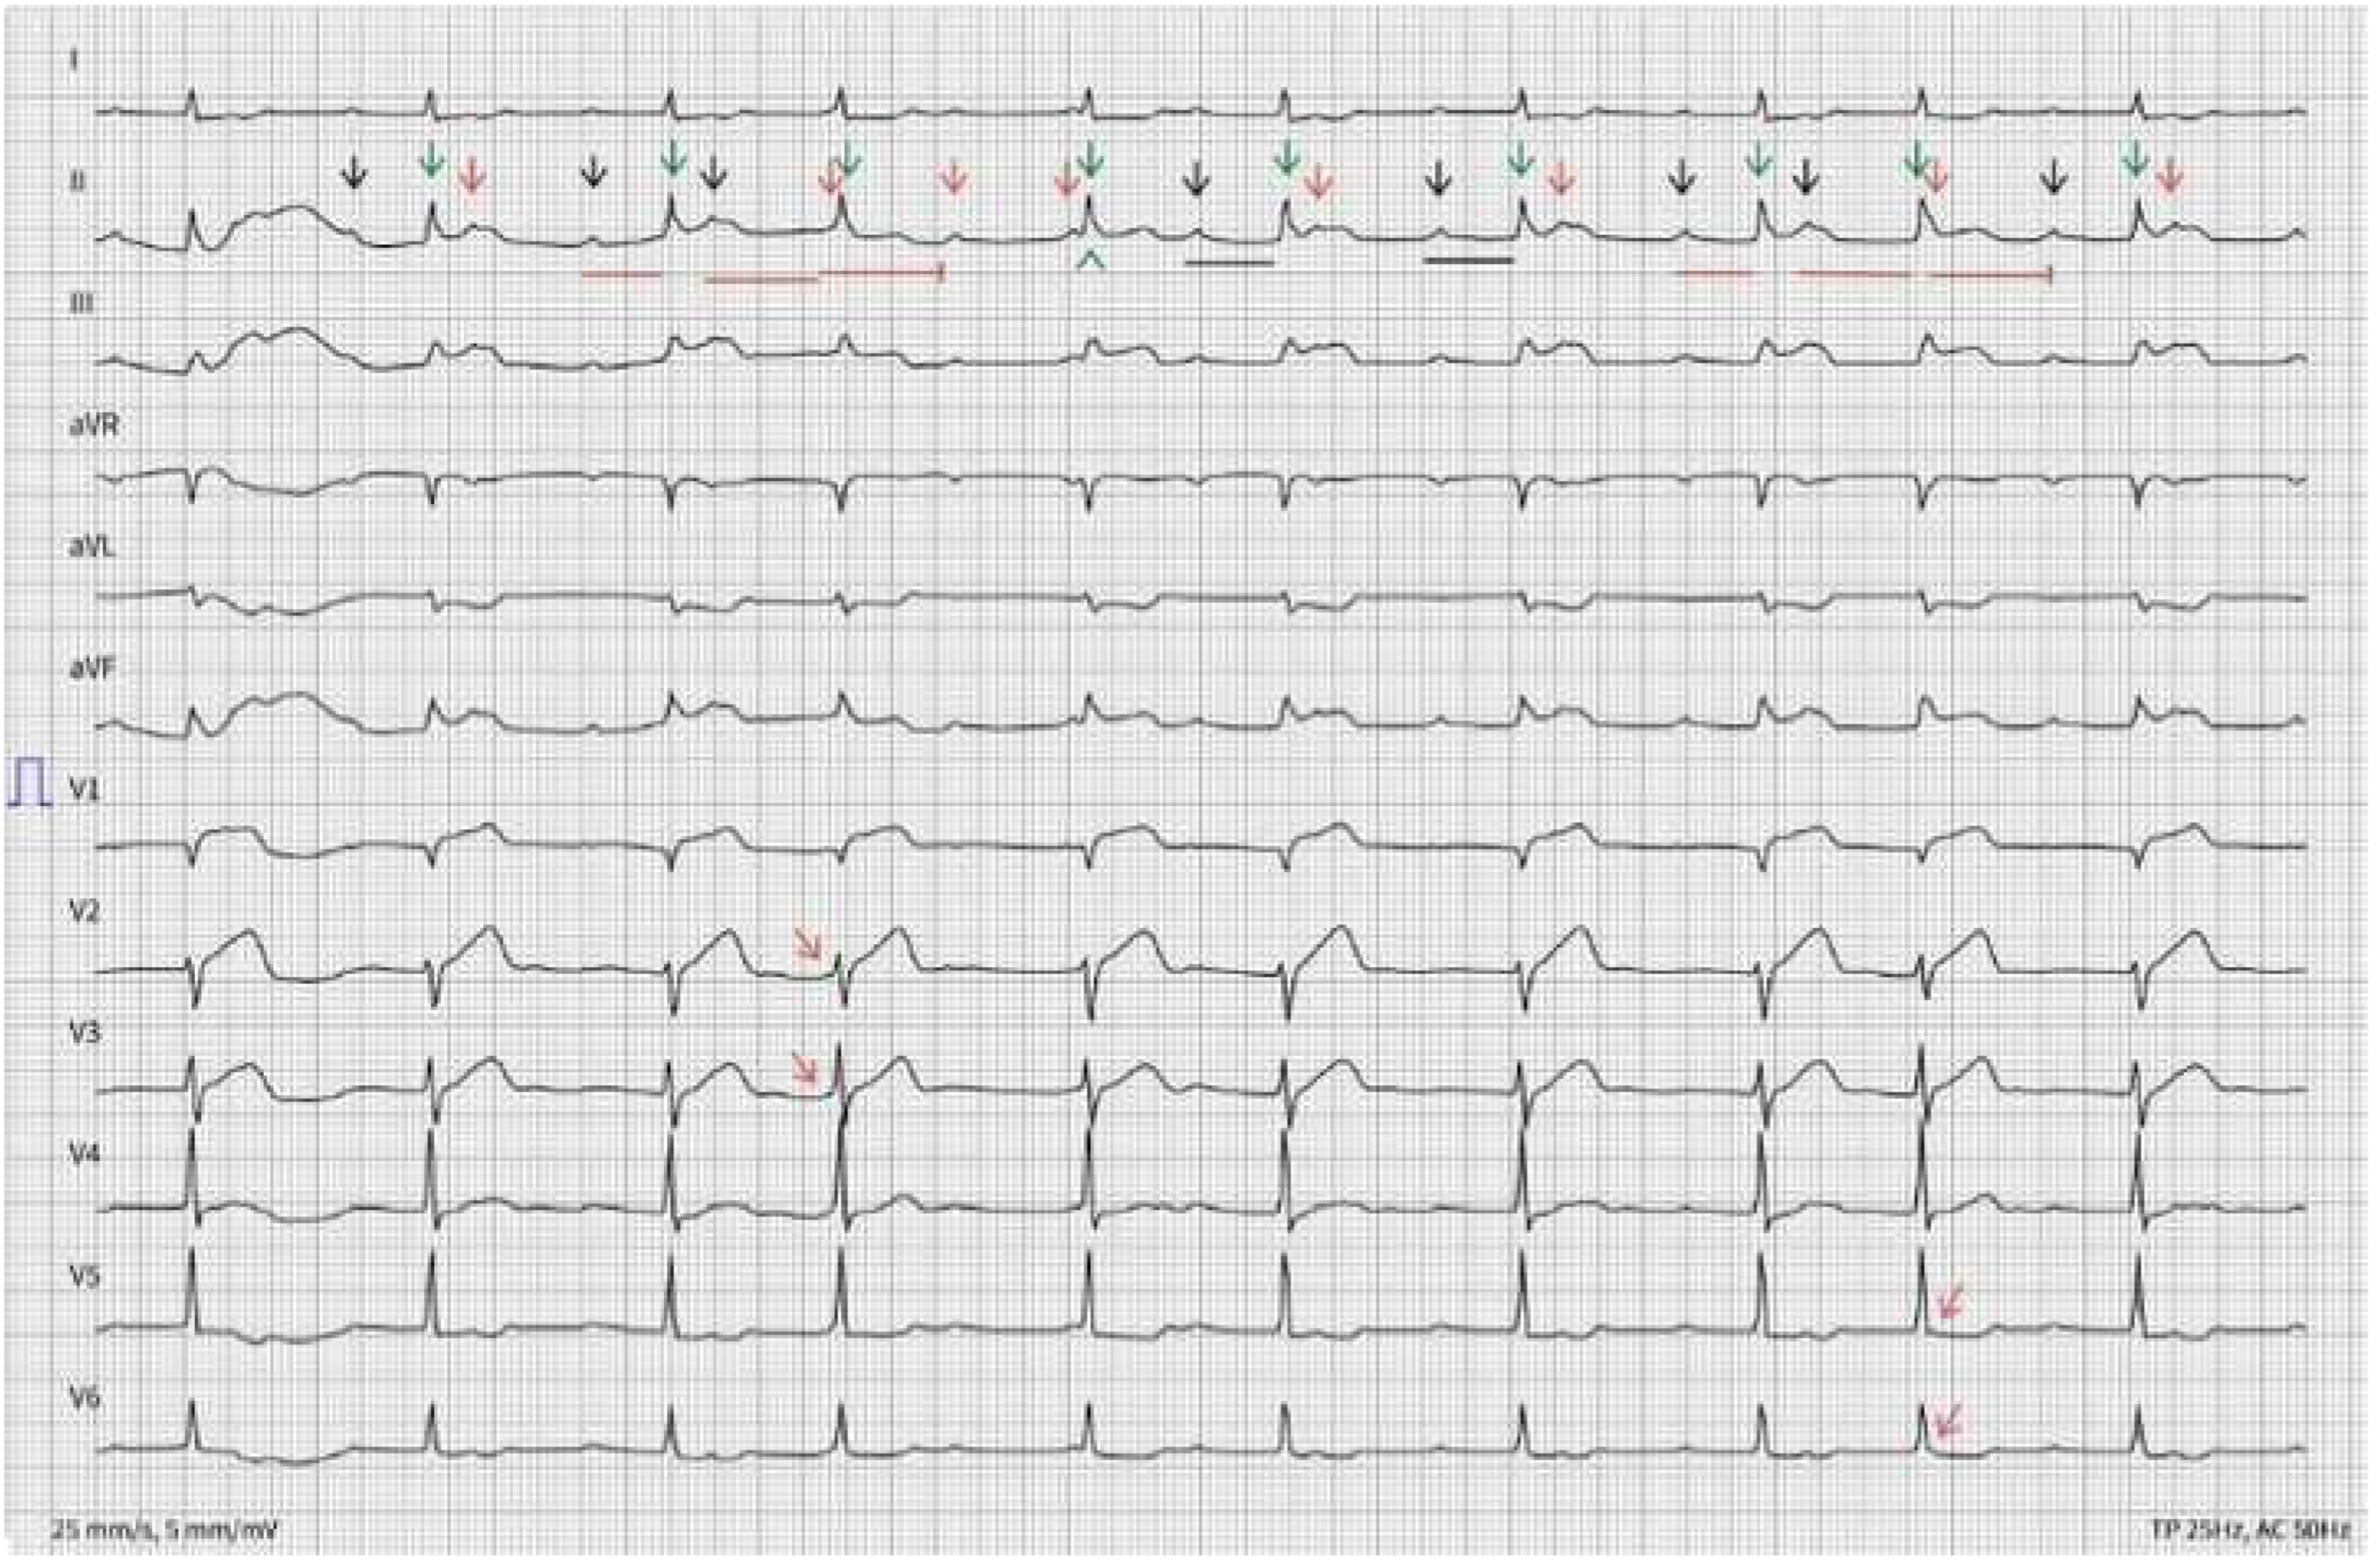

A 56-year-old man with history of hypertension, diabetes mellitus type 2 and chronic kidney disease is evaluated in the emergency department due to nausea, abdominal pain, excessive sudation and lightheadedness for the past 4 h. Physical examination is unremarkable. The following ECGs (ECG A and B) are obtained.

There is an irregular rhythm with a ventricular rate of 61 bpm. QRS complexes are narrow. Big amplitude T-waves are seen in V1 through V3 (circled). There is significant ST segment elevation in leads II-III, aVF and V1 (red arrowheads) with reciprocal ST segment depression in leads aVL, V5 and V6 (black arrowheads). An increased number of P waves (black and red arrows, corresponding respectively to conducted and non-conducted P waves), compared to the number of QRS complexes (green arrows), can be counted. The PP interval is regular. An increasing PR interval (red lines with increasing length) is measured, with a resulting non-conducted P wave (2nd red arrow and terminated red line), compatible with a Wenckebach phenomenon. The non-conducted P wave is merged in the QRS complex and can be better visualized in V2 and V3 (leftward bending red arrows). The following QRS complex (green arrowhead) results from conduction with a very long PR interval or represents a junctional escape beat. The PR interval of the preceding P wave is indeed too short to result in AV conduction. Thereafter, a 2:1 block occurs for 2 cycles (underlined in black), followed by a repeat Wenckebach phenomenon (red lines with increasing length and finally terminated). The blocked P wave is hidden in the QRS complex and can be better spotted in V5 and V6 (rightward bending red arrows).

Based on these ECGs, an inferior ST-segment elevation myocardial infarction (STEMI) with associated atrioventricular (AV) nodal conduction abnormalities is suspected. The ST-segment elevation in lead III > II associated with an ST-segment elevation in V1 suggest an associated right ventricular infarction [1]. Additionally, a 2nd degree Mobitz type I AV block with 2:1 ventricular conduction is present. An intranodal rather than infranodal AV block is suggested, due to the prolonged PR interval and documented Wenckebach phenomenon with 3:2 conduction [2]. A proximal to mid-right coronary artery (RCA) lesion is probable, with resulting ischemia of the right ventricle, as well as the AV nodal artery perfusion area.

ECG B with answer

Cardiovascmed 22 00001 g005